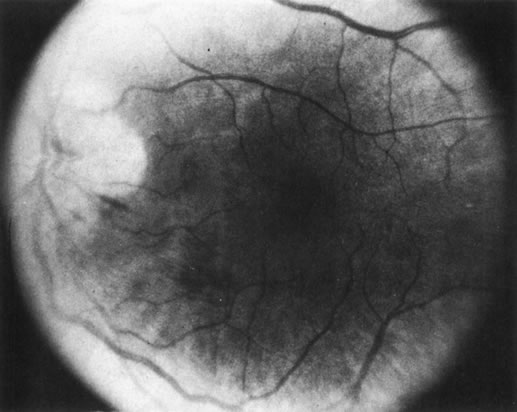

1. The intraocular findings in primary intraocular–CNS lymphoma may simulate a diffuse uveitis, usually with a plethora of vitreous cells and often with virtually pathognomonic yellowish white chorioretinal infiltrates (Fig. 20). Less common clinical presentations can mimic toxoplasmosis, acute retinal necrosis, a branch vein occlusion, or various forms of retinal vasculitis.

Fig. 20. Yellowish white chorioretinal infiltrate typical of primary intraocular lymphoma (erroneously termed ocular reticulum cell sarcoma). (Char DH: Clinical Ocular Oncology. 2nd ed. Philadelphia, Lippincott-Raven, 1996.)